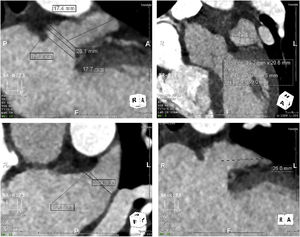

Procedure protocolTo characterize the anatomy and morphology of the LAA and to exclude the presence of thrombus, all patients underwent a cardiac computed angiography (CTA) (example in Figure 1) imaging assessment 48 hours before the procedure or TEE with conscious sedation in the cath lab immediately before LAAO, when CTA imaging was not available.

Three types of device (Figure 2) were used for LAAO: Amplatzer Cardiac Plug (ACP) or Amulet (St. Jude Medical), WATCHMAN (Boston Scientific), and LAmbre (Lifetech Scientific). Device sizing was mainly based on the pre-procedural CTA scan or TEE assessment, bearing in mind the angiographic and ICE-acquired dimensions.